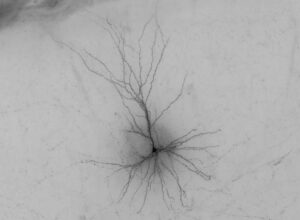

Unravelling the contributions of all those genes is no easy task. Previous studies had identified neurons as the broad type of cell driving the disease, Bakken said, but their hope was to drill down further into the disease by pinpointing a more specific class or classes of cells responsible.

The research team, which was led by Jens-Hjerling-Leffler, Ph.D., and Patrick Sullivan, M.D., of the Karolinska Institutet, asked which cell types in mouse and human brains are actually using the hundreds of genes associated with schizophrenia. To do this, they turned to large datasets of mouse and human brain gene expression that measure the complete sets of genes used in individual cells. Different sets of genes are responsible for the function of different types of cells, and by looking at the activity of genes linked to schizophrenia the researchers could pinpoint which cells would be affected if those genes were disrupted.

Comparing information across the datasets, the researchers pulled out the three distinct types of neurons that turn on the schizophrenia-associated genes. The Seattle and Sweden teams are now trying to pin down the affected cell types with even higher specificity.